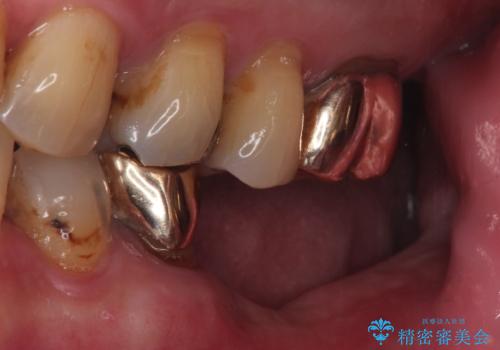

- 「奥歯の銀歯が取れた」を主訴に来院された患者さんです。

診査診断を行った結果、歯が折れた位置が深く、虫歯にもなっていたため抜歯後、インプラントで治療を行いました。